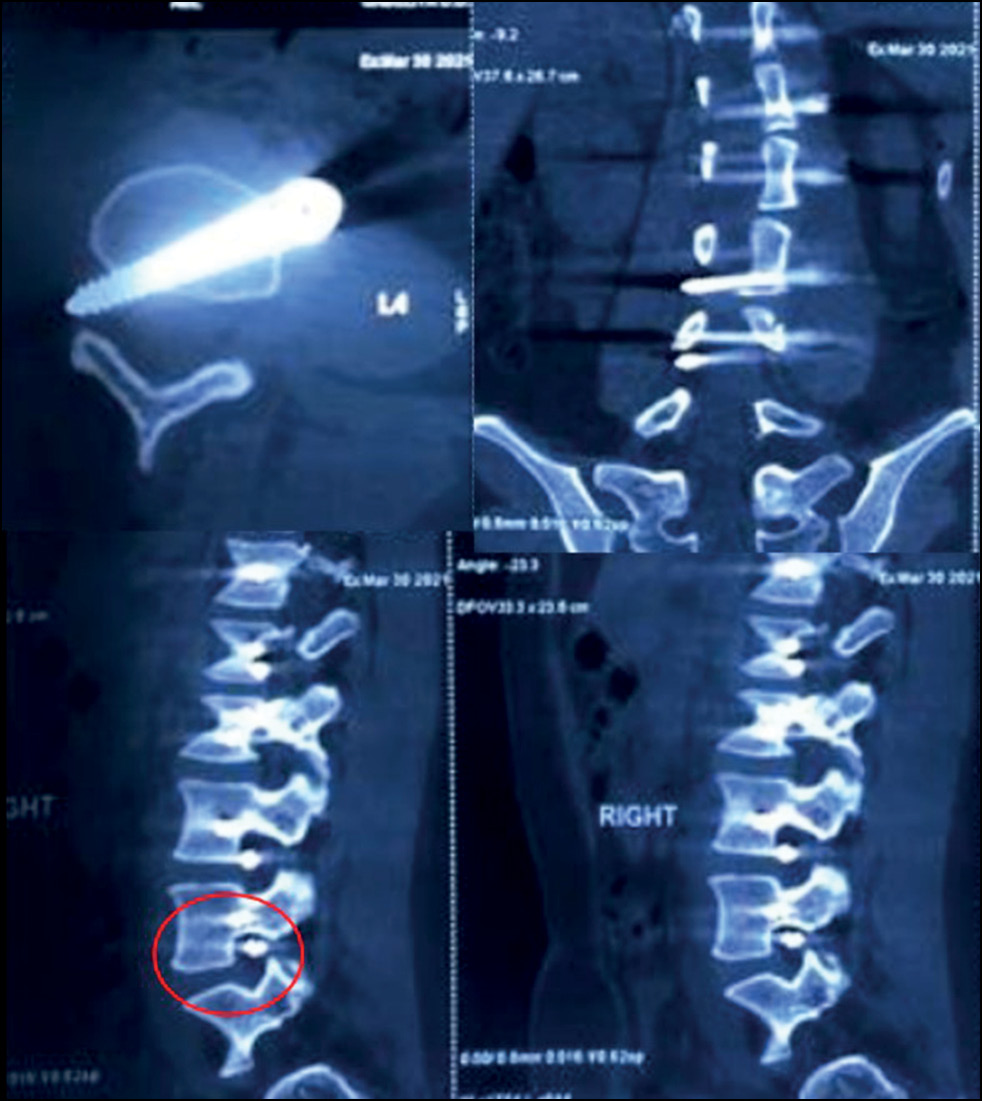

Six patients underwent revision surgery. Although all patients achieved satisfactory results, access-related complications were observed, including pulmonary complications such as hemothorax, chylothorax, and pneumothorax. One patient required revision because of hemothorax. Two patients experienced chylothorax postoperatively, which was managed conservatively with diet and octreotide. Neuropathy was observed after lumbar/ thoracolumbar correction in one case necessitating revision. Malposition was observed in two patients, requiring revision. The screw was incorrectly placed in L4 in one patient, with the 45-mm screw entering the foraminal foramen on the opposite side, accompanied by radiculopathy requiring repeated surgical intervention (Fig. 3).

Fig. 3. CT scans of a 16-year-old female patient after performing lumbar spine anterior dynamic scoliosis correction: the presence of the anterior part of the screw in the area of the foraminal opening L4-L5 is noted with the condition of the L4 root compression.